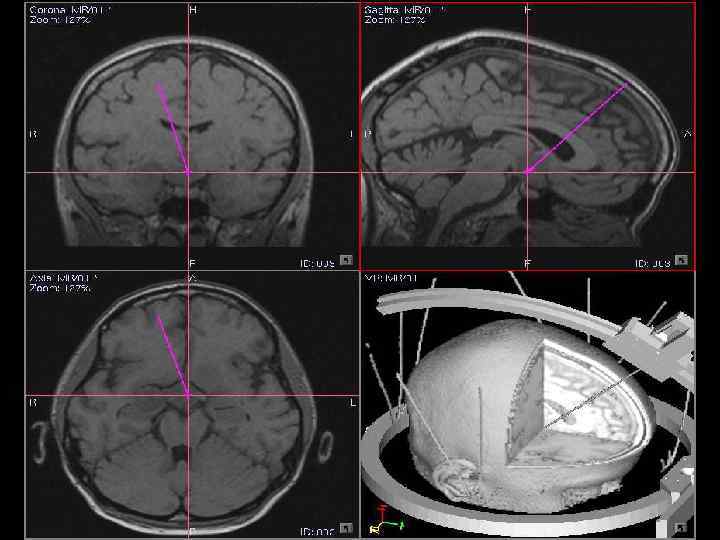

Использование навигационной системы 40

Стереотаксическая операция с применением автономного криоприбора под контролем компьютерного томографа интраоперационного электрофизиологического мониторинга 47